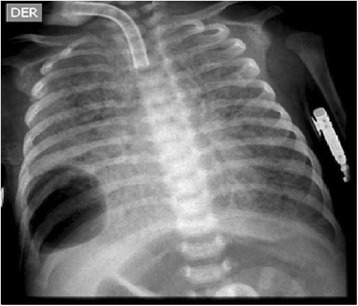

We describe the case of a full-term Colombian newborn baby boy who was the product of a primigravid mother, and non-consanguineous parents of mixed race ancestry (Mestizo). Fetal monitoring at the 37th week gestational age showed continuous decelerations. A caesarean section was performed and he was delivered with severe respiratory depression. Management with noninvasive positive-pressure ventilation was started without success. He was transferred to our intensive care unit and intubation was performed. An echocardiogram showed moderate pulmonary hypertension. Chest X-rays showed complete bilateral opacity of both lungs. Initial treatment with artificial surfactant was offered without success (Fig. 1).

Fig. 1.

Anteroposterior chest radiograph from a newborn baby boy showing bilateral diffuse hazy granular pulmonary opacification